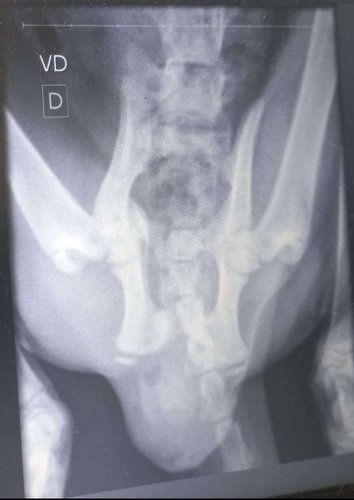

Massss, sofreu uma queda no dia 01.02, no dia que completou 3 meses aproximadamente, sofreu uma fratura e precisará passar por cirurgia.

Abaixo seguem as radiografias